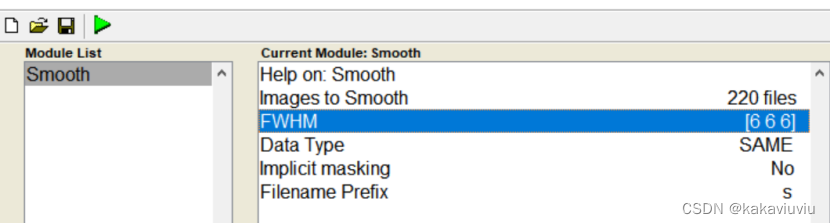

(5)平滑

把上一步的文件wra开头的导入,平滑核6 6 6(体素的2-3倍,一般就用2倍)

run

得到swra开头文件